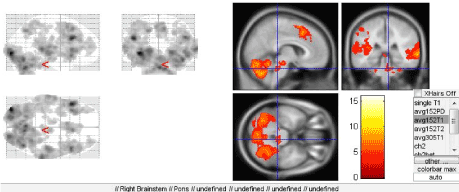

When regular people without musical training perceive music, it is primarily emotional perception of the melody signals. In contrast, musicians perceive a melody as “speech” consisting of meaningful elements with their own sense. The emotional component of music perception is provided by the brain structures combined into the Papez circuit, which a part of the limbic system. Here we should also mention the frontal lobes of the cerebral hemispheres and their connections with non-specific brainstem structures that exert both activating and deactivating effects on the cortex, including the speech-related areas (Figure 7A). Consideration of this fact along with the feedback with executive speech organs once resulted in actual extension and deepening of the understanding of the organization of speech and definition of its afferent and efferent forms [8].

Figure 7. Activation of brainstem structures

All three paradigms were designed to study the speech prosody, i.e. direct involvement of extralinguistic speech components-speech intonation, rate, pitch and tone. Our results strongly suggest the connection between the prosody (in all tests) and the limbic system at different levels, which is directly related to the emotional constituent of the speech. A separate role is played by the deep brain structures, thalamus in particular, which was found to be most significantly activated during two of three paradigms (for determination of rhythm and intonation) (Figure 7B).